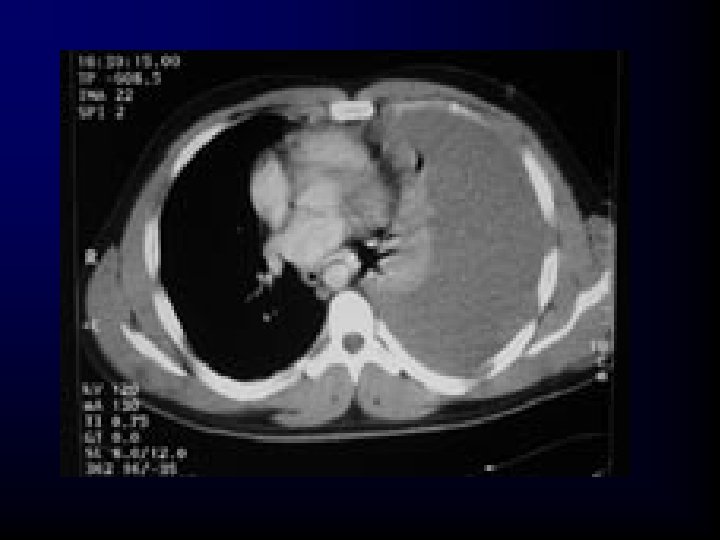

Traumatic Aortic Rupture • Incidence – Blunt trauma • Rapid deceleration in high-speed motor vehicle crashes • Falls from great heights • Crushing injuries 15% of all blunt trauma deaths

Traumatic Aortic Rupture Morbidity/Mortality • 80% to 90% of these patients die at the scene as a result of massive hemorrhage. – About 10% to 20% of these patients survive the first hour. • Bleeding is tamponaded by surrounding adventitia of the aorta and intact visceral pleura. • Of these, 30% have rupture within 6 hours.

Traumatic Aortic Rupture Pathophysiology • Patients who are normotensive should have limited replacement fluids to prevent an increase in pressure in the remaining aortic wall tissue.

Traumatic Aortic Rupture Assessment Findings • Upper-extremity hypertension with absent or decreased amplitude of femoral pulses – Thought to result from compression of the aorta by the expanding hematoma • Generalized hypertension – Secondary to increased sympathetic discharge • Retrosternal or interscapular pain

Traumatic Aortic Rupture Assessment Findings • About 25% have a harsh systolic murmur over the pericardium or interscapular region • Paraplegia with a normal cervical and thoracic spine (rare)

Traumatic Aortic Rupture Assessment Findings • • Dyspnea Dysphagia Ischemic pain of the extremities Chest wall contusion

Aortic Injury : Suspicion • Mechanism – Falls> 3 m – Major decelaration/acceleration • SIGNS – Neck hematoma – Assymetic pulse or BP – Radiofemoral delay – Severe searing pain

Aortic Injury: CXR Signs • • • Mediastinum > 8 cm Abnormal Aortic contour Opaque artopulmonary window Apical cap Mediastinal displacement Fracture of first rib or scapula